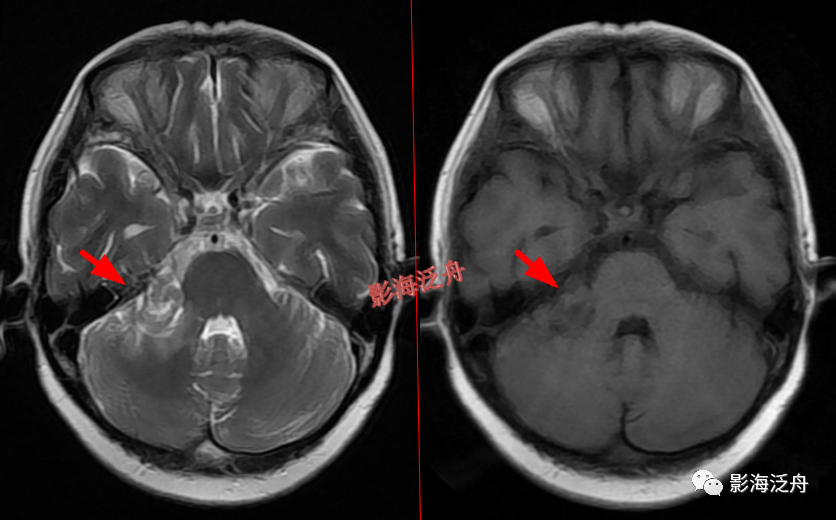

右侧侧脑室体部囊性占位(红箭),整体信号与脑脊液一致,病灶边缘部分显示,透明隔稍移位。

灰质移位,患者既往有癫痫

病史。右侧侧脑室前角及左侧侧脑室后角可见异位的灰质结节(红箭),与大脑皮层下的灰质信号一致(绿箭),灰质异位患者多伴有癫痫症状。